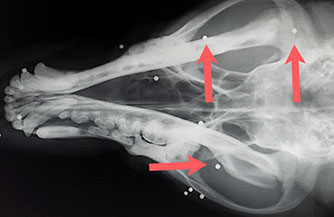

Schrotkugeln im Kopf eines Jagdhundes